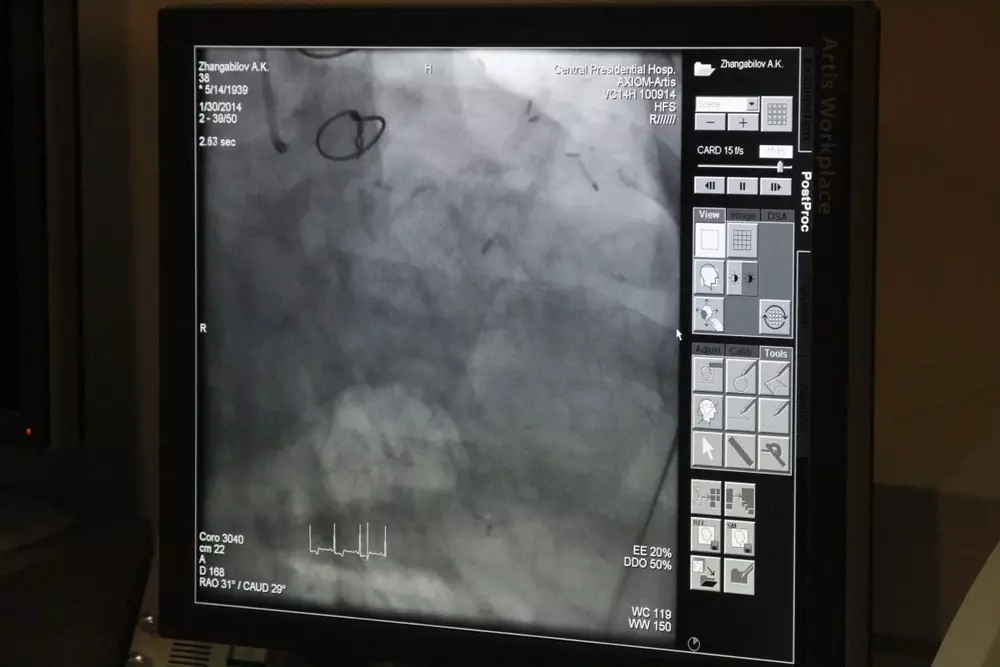

Удалять тромб легких за 20 минут научились врачи "совминовской" больницы в Алматы Кадр видеозаписи проведенной операции. Фото©Алишер Ахметов

Тромб легких удалили пациенту, который находился в критическом состоянии, врачи больницы Управления делами Президента в Алматы, передает корреспондент Tengrinews.kz. Мужчине в возрасте 28 лет угрожала сердечно-легочная недостаточность, поскольку тромб легких продвинулся из кровеносных сосудов в ноге и закупорил кровеносную систему дыхательных органов. Врачи провели операцию с использованием специального прибора - эндоскопа. Аппарат был введен в тело пациента через сосуды и позволил обойтись без больших разрезов. С помощью эндоскопа врачи смогли добраться до места закупорки и растворить образование с помощью лекарства. Отмечается, что пациент, которому удалили тромб легких, во время операции находился в сознании. "У пациента начались проблемы с дыханием, состояние ухудшалось. Появилось явление кровохарканья. Он обратился к нам. Во время исследования было выявлено, что у него есть нарушение кровоснабжения", - рассказал врач. Как сообщил замглавврача больницы Управления делами Президента Данияр Амангалиев, теперь медики могут проводить лечение тромба легких за 20 минут. Отметим, методы проведения малотравматичных операций в клинике внедрил хирург Нуртас Казыбаев еще в 1996 году. По словам Амангалиева, такие операции проводятся только в экстренных случаях. "В группе риска в основном люди, страдающие варикозным расширением вен нижних конечностей и люди, у которых нарушено состояние крови", - сказал врач. По его словам, такая операция может проводиться по государственному заказу. По словам консультанта больницы Управления делами Президента Ахметжана Сугралиева, сколько таких операций может потребоваться казахстанцам - неизвестно. Но он отметил, что если опираться на данные по статистике таких случаев в США, тромб легких может угрожать до тридцати тысячам казахстанцев ежегодно. По словам Сугралиева, заболевание характеризуется травмами сосудов, легочной гипертензией. Во многих случаях отмечается высокая летальность.